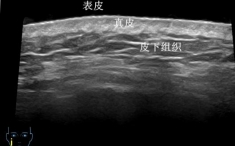

一、皮肤结构的精细呈现

我们的皮肤从外到内分为表皮、真皮、皮下组织三层,就像一层薄外套裹着两层“保暖层”。在超高频探头下,薄薄的皮肤可以变成一张 “皮肤剖面图” ,不仅可以看到表皮、真皮、皮下组织的结构,精确测量其厚度,还可以清晰显示其内的毛发、毛囊、皮脂腺等肉眼及普通超声无法识别的结构。